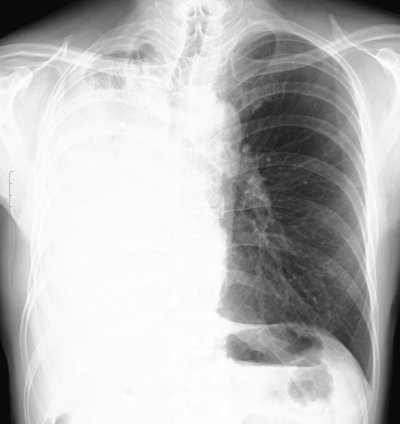

46 歳の男性。呼吸困難を主訴に来院した。1か月前から胸部違和感と労作時呼吸困難とを自覚していたが、徐々に増強するため来院した。1週間前までは胸部にヒューヒューという音がしていたが、現在は消失しているという。既往歴に特記すべきことはない。喫煙は 40 本/日を 26 年間。胸部エックス線写真を示す。

異常所見の原因として最も可能性が高いのはどれか。

a. 肺癌

b. 気胸

c. 血胸

d. 胸膜炎

e. 胸膜中皮腫